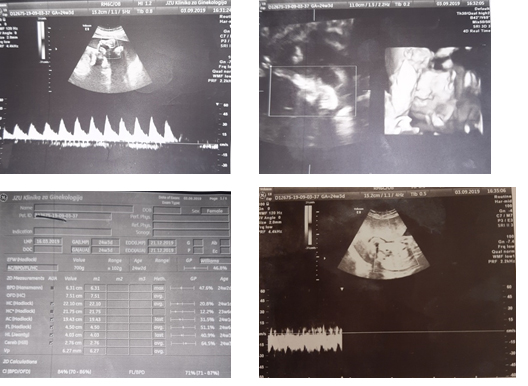

At the University Clinic of Gynecology and Obstetrics, the patient appears for the first time at 24.3 weeks of gestation, in an outpatient clinic where she has a scheduled screening examination in the second trimester.

During the examination, it was established that it was a eutrophic fetus, without major anomalies, normal fetoplacental flow, normal fetal movements. A recommendation was given to do control examinations at the Clinic for Pulmonology, Orthopedics, Cardiology and Nephrology. At the control examination after 1 week, the patient had an examination only at the Pulmonology and Orthopedics Clinic, where appropriate therapy was prescribed. Laboratory analyzes were in reference values. Blood pressure was regulated by antihypertensive therapy.

During hospitalization, high values of the angiogenic factors sFLT/PLGF up to 793.05, proteinuria 0.79g/L and malignant hypertension regulated by double antihypertensive therapy were determined. NST was reactive. The ultrasound finding was normal, the fetus had a normal fetoplacental flow.